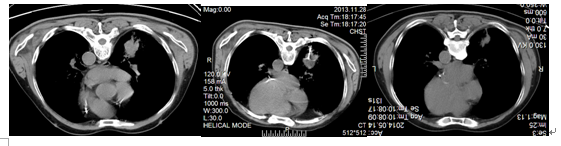

(二)患者、男、71岁,2013年11月CT+病检诊断右侧周围性肺癌,因患者长期糖尿病,手术切除风险大,于11月在我院行CT引导下行射频消融治疗,术后结合中药治疗,半年复查病灶明显缩小!